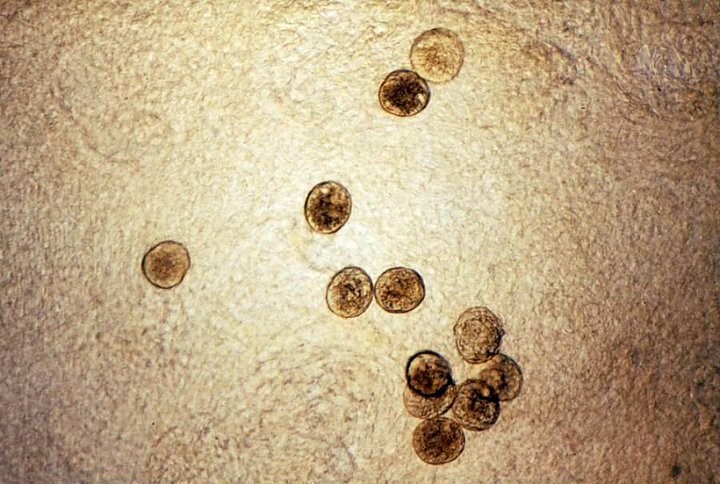

Hình 2: Trứng S.mekongi (nguồn: http://web.stanford.edu/) | Hình 3: Ấu trùng đuôi chẻ (nguồn: http://web.stanford.edu/) |

Trứng gần giống hình cầu, nhỏ so với Schistosoma khác. Mỗi ngày trung bình sán đẻ 95 trứng, thấp hơn đáng kể so với các Schistosoma khác, S. japonicumcó thể đẻ 250 trứng mỗi ngày.

Người bị nhiễm sán được xác định có trứng trong mẫu phân. Trứng S. mekongi được phân biệt với S. japonicum dựa trên kích thước, trứng S. mekongi nhỏ hơn, đường kính dao động từ 30-55μm, trong khi trứng của S. japonicum khoảng 50-65μm.

Hình 6:Trứng của S. mekongi (nguồn: http://web.stanford.edu)